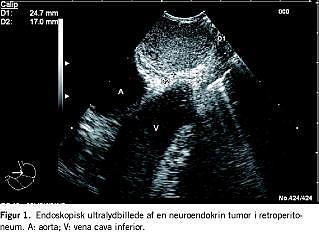

EUS viste en (eller flere) tumor(er) hos 13 patienter (Figur 1 ). Alle patienter, hos hvem man med EUS havde påvist en tumor, gennemgik efterfølgende operation, hvor man fandt en eller flere tumorer hos 12 patienter, mens der var normale forhold hos en. Ni (75%) patienter havde deres tumor(er) lokaliseret i pancreas (Figur 2 ), mens tre (25%) havde tumorer lokaliseret i retroperitoneum. Mikroskopi viste NET af forskellig histologisk art (n = 11) og adenokarcinom (n = 1) (Tabel 1 ). Den præoperative diagnostik fremgår ligeledes af Tabel 1. Otte af de 13 patienter havde fået udført ekstern UL-skanning, som viste normale forhold hos fire (50%), mens syv havde fået udført en CT, hvor der ikke blev påvist tumor hos fire (57%). Herudover var der hos to patienter foretaget MR-skanning, hvor man påviste tumor hos en (en patient med en ikkehormonelt aktiv tumor), men ikke fandt tumor hos en, hvor man med EUS senere påviste en tumor (en patient med et insulinom).